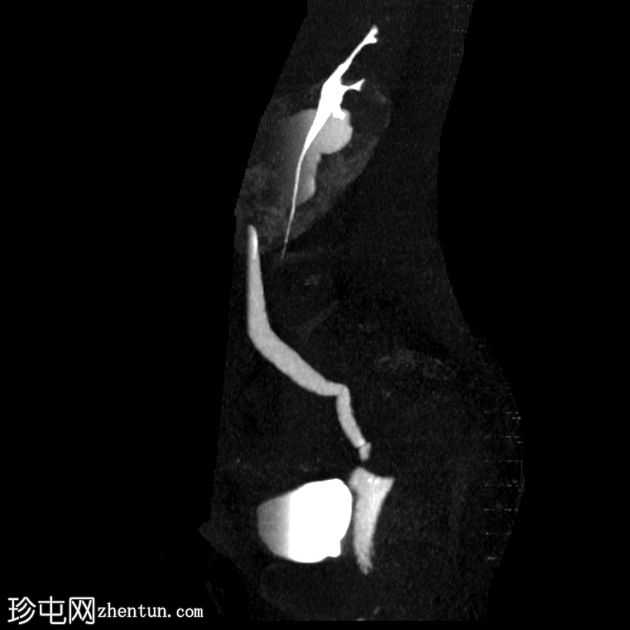

矢状位肾排泄期

右肾中度肾积水,输尿管积水延伸至S4椎体水平。延迟期图像显示阴道残端扩张并充满造影剂,与右侧远端输尿管相通。

延迟期图像显示右侧肾盂呈斑片状强化,提示延迟性肾图,可能由远端梗阻引起。